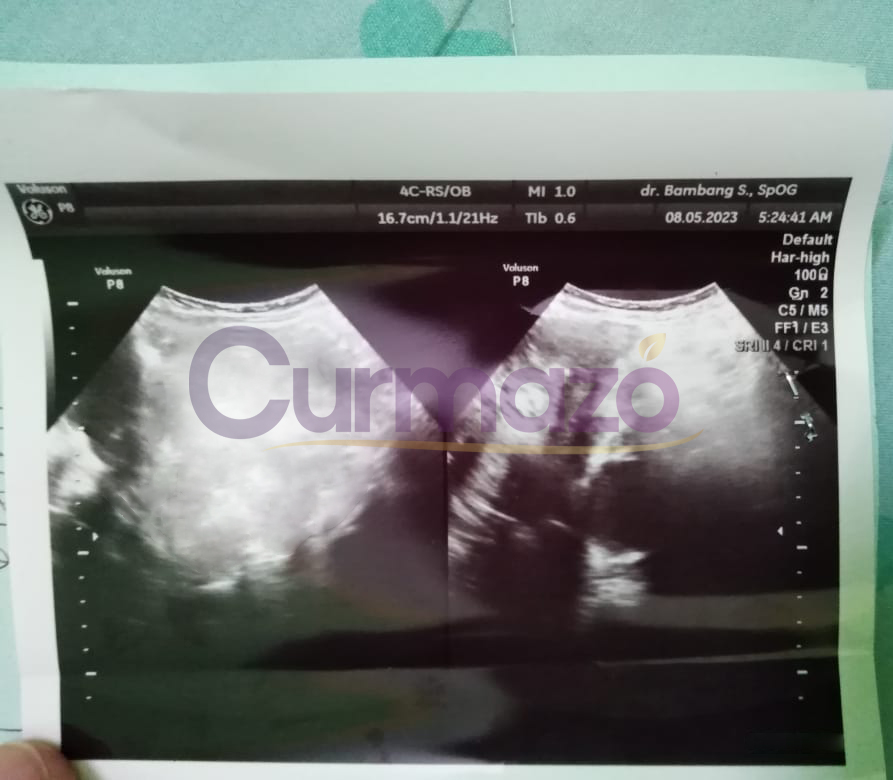

Hampir 4 bulan pengobatan saya sudah tidak merasakan gejala seperti sebelumnya, haid sudah lancar dan teratur. 8 Mei 2023 Saya coba menjalani pemeriksaan, hasilnya sangat luar biasa kista berukuran 7,76 x 9,56 cm tersebut hilang total.

Bulan ke-3, Saya cek ke dokter lagi. Hasilnya sangat mengejutkan, kista berukuran 4,7 x 4,1 c,m hilang total.